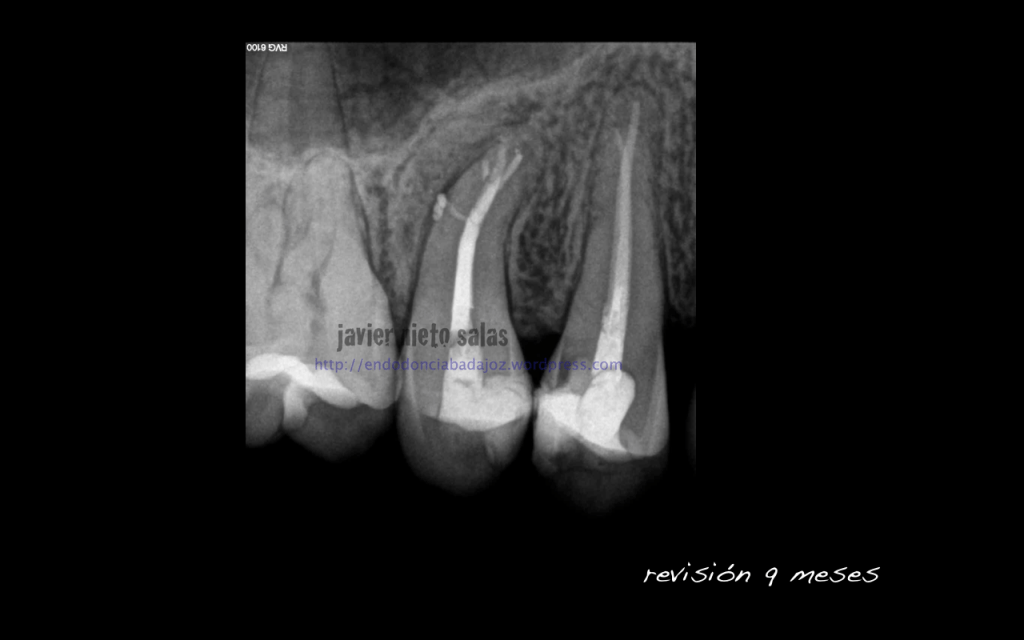

Volvemos a ver a la paciente a los 9 meses y vemos como la lesión ha regenerado correctamente y la lesión en furca va desaparecido.